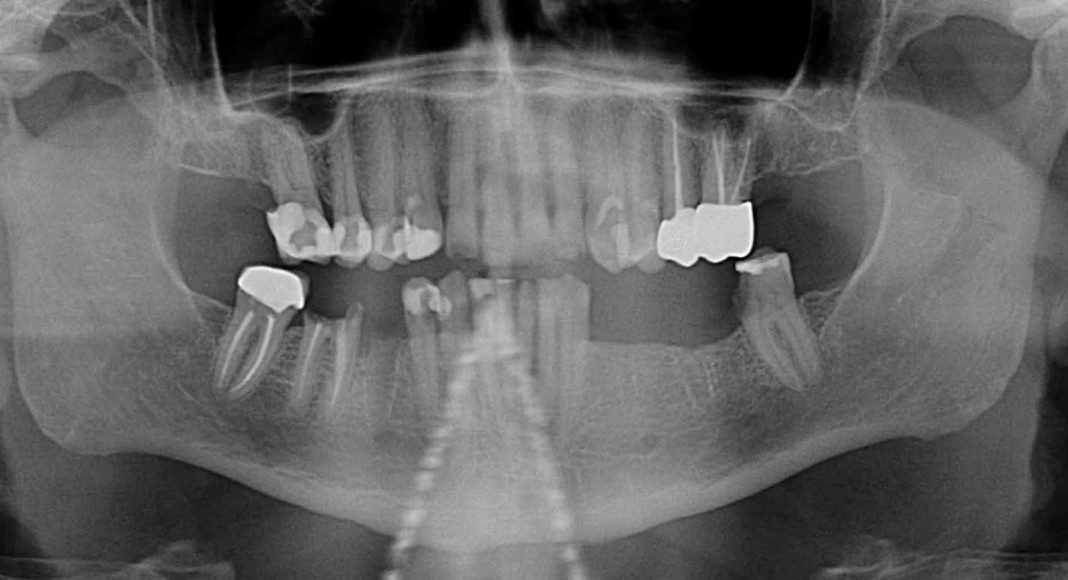

Progress panoramic x-ray. This x-ray really tells the story, visually. Notice the presence of teeth and implants. When immediate implant stability is not high enough to support the temporary bridge, we use some teeth as abutments (resting spots) for the temporary bridge. This prevents the patient from ever having to wear a temporary denture. This transitional phase allows the patient to be very comfortable while the implants are gaining stability (microscopic adhesion of the implant to the bone) and the temporary bridge is cemented to the strategic teeth.

2 months later, teeth and implants after temporary is removed. The implants are now ready to serve as the anchors for the temporary bridge. At this second surgical appointment the strategic teeth are extracted, additional implants placed (if necessary) and the temporary bridge converted to the implants.